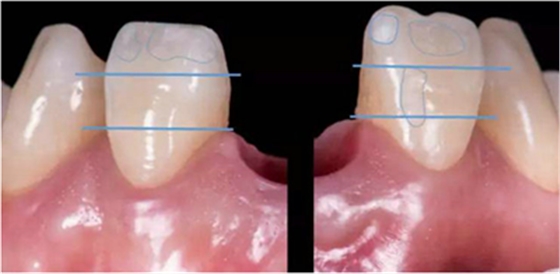

種植過(guò)渡義齒試戴,調(diào)整唇側(cè)凸度,切端位置

患者剛戴入過(guò)渡義齒時(shí),發(fā)現(xiàn)牙齦泛白,范圍不超過(guò)鄰牙終點(diǎn)。若患者休息10分鐘后,牙齦顏色恢復(fù)正常,則說(shuō)明穿齦輪廓設(shè)計(jì)合理。

種植過(guò)渡義齒戴牙后1個(gè)月,患者希望改善義齒美觀度,并進(jìn)一步減少唇側(cè)凸度

患者試戴1個(gè)月后,發(fā)現(xiàn)牙齦塑性效果良好,過(guò)渡義齒穿齦部分不需要修改

種植過(guò)渡義齒戴牙后3個(gè)月,牙齦形態(tài)穩(wěn)定

過(guò)渡義齒制作完成及試戴

過(guò)渡義齒佩戴3個(gè)月后